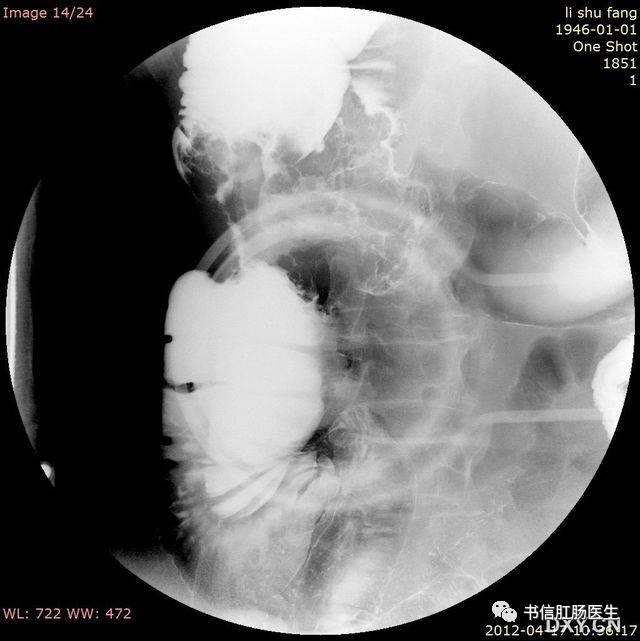

3.咖啡豆征(莱豆征、弯管征)

★ 一例绞窄性性肠梗阻形似「咖啡豆」

■ 影像表现:仰卧位腹部平片上表现为肠管透亮区形成类似咖啡豆样的形态。

■ 征象解析:肠管部分性嵌闭时,扩张的闭襻内因充气而透明,正中为折叠后相靠近的两端肠内壁形成的条状致密带,形如咖啡豆,称咖啡豆征。咖啡豆征是乙状结肠扭转的经典 X 线表现,是因为乙状结肠闭襻积气扩张,肠管的内侧壁并列形成咖啡豆征的裂隙,而扩张肠管的侧壁形成咖啡豆征的外侧壁。

■ 讨论:咖啡豆征可以用来描述小肠闭襻型梗阻,但更多用于描述乙状结肠的闭襻型梗阻。假如仰卧位腹部平片不能明确诊断时,行单纯的钡剂灌肠检查,在扭转的部位会出现钡柱突然中断,而呈鸟嘴样或鸟嘴征。但钡剂强制性通过扭转部位可能会导致穿孔或使不完全梗阻转变成完全梗阻。当患者出现肠缺血或肠穿孔时,不能行钡剂灌肠检查,而应立即行手术治疗。